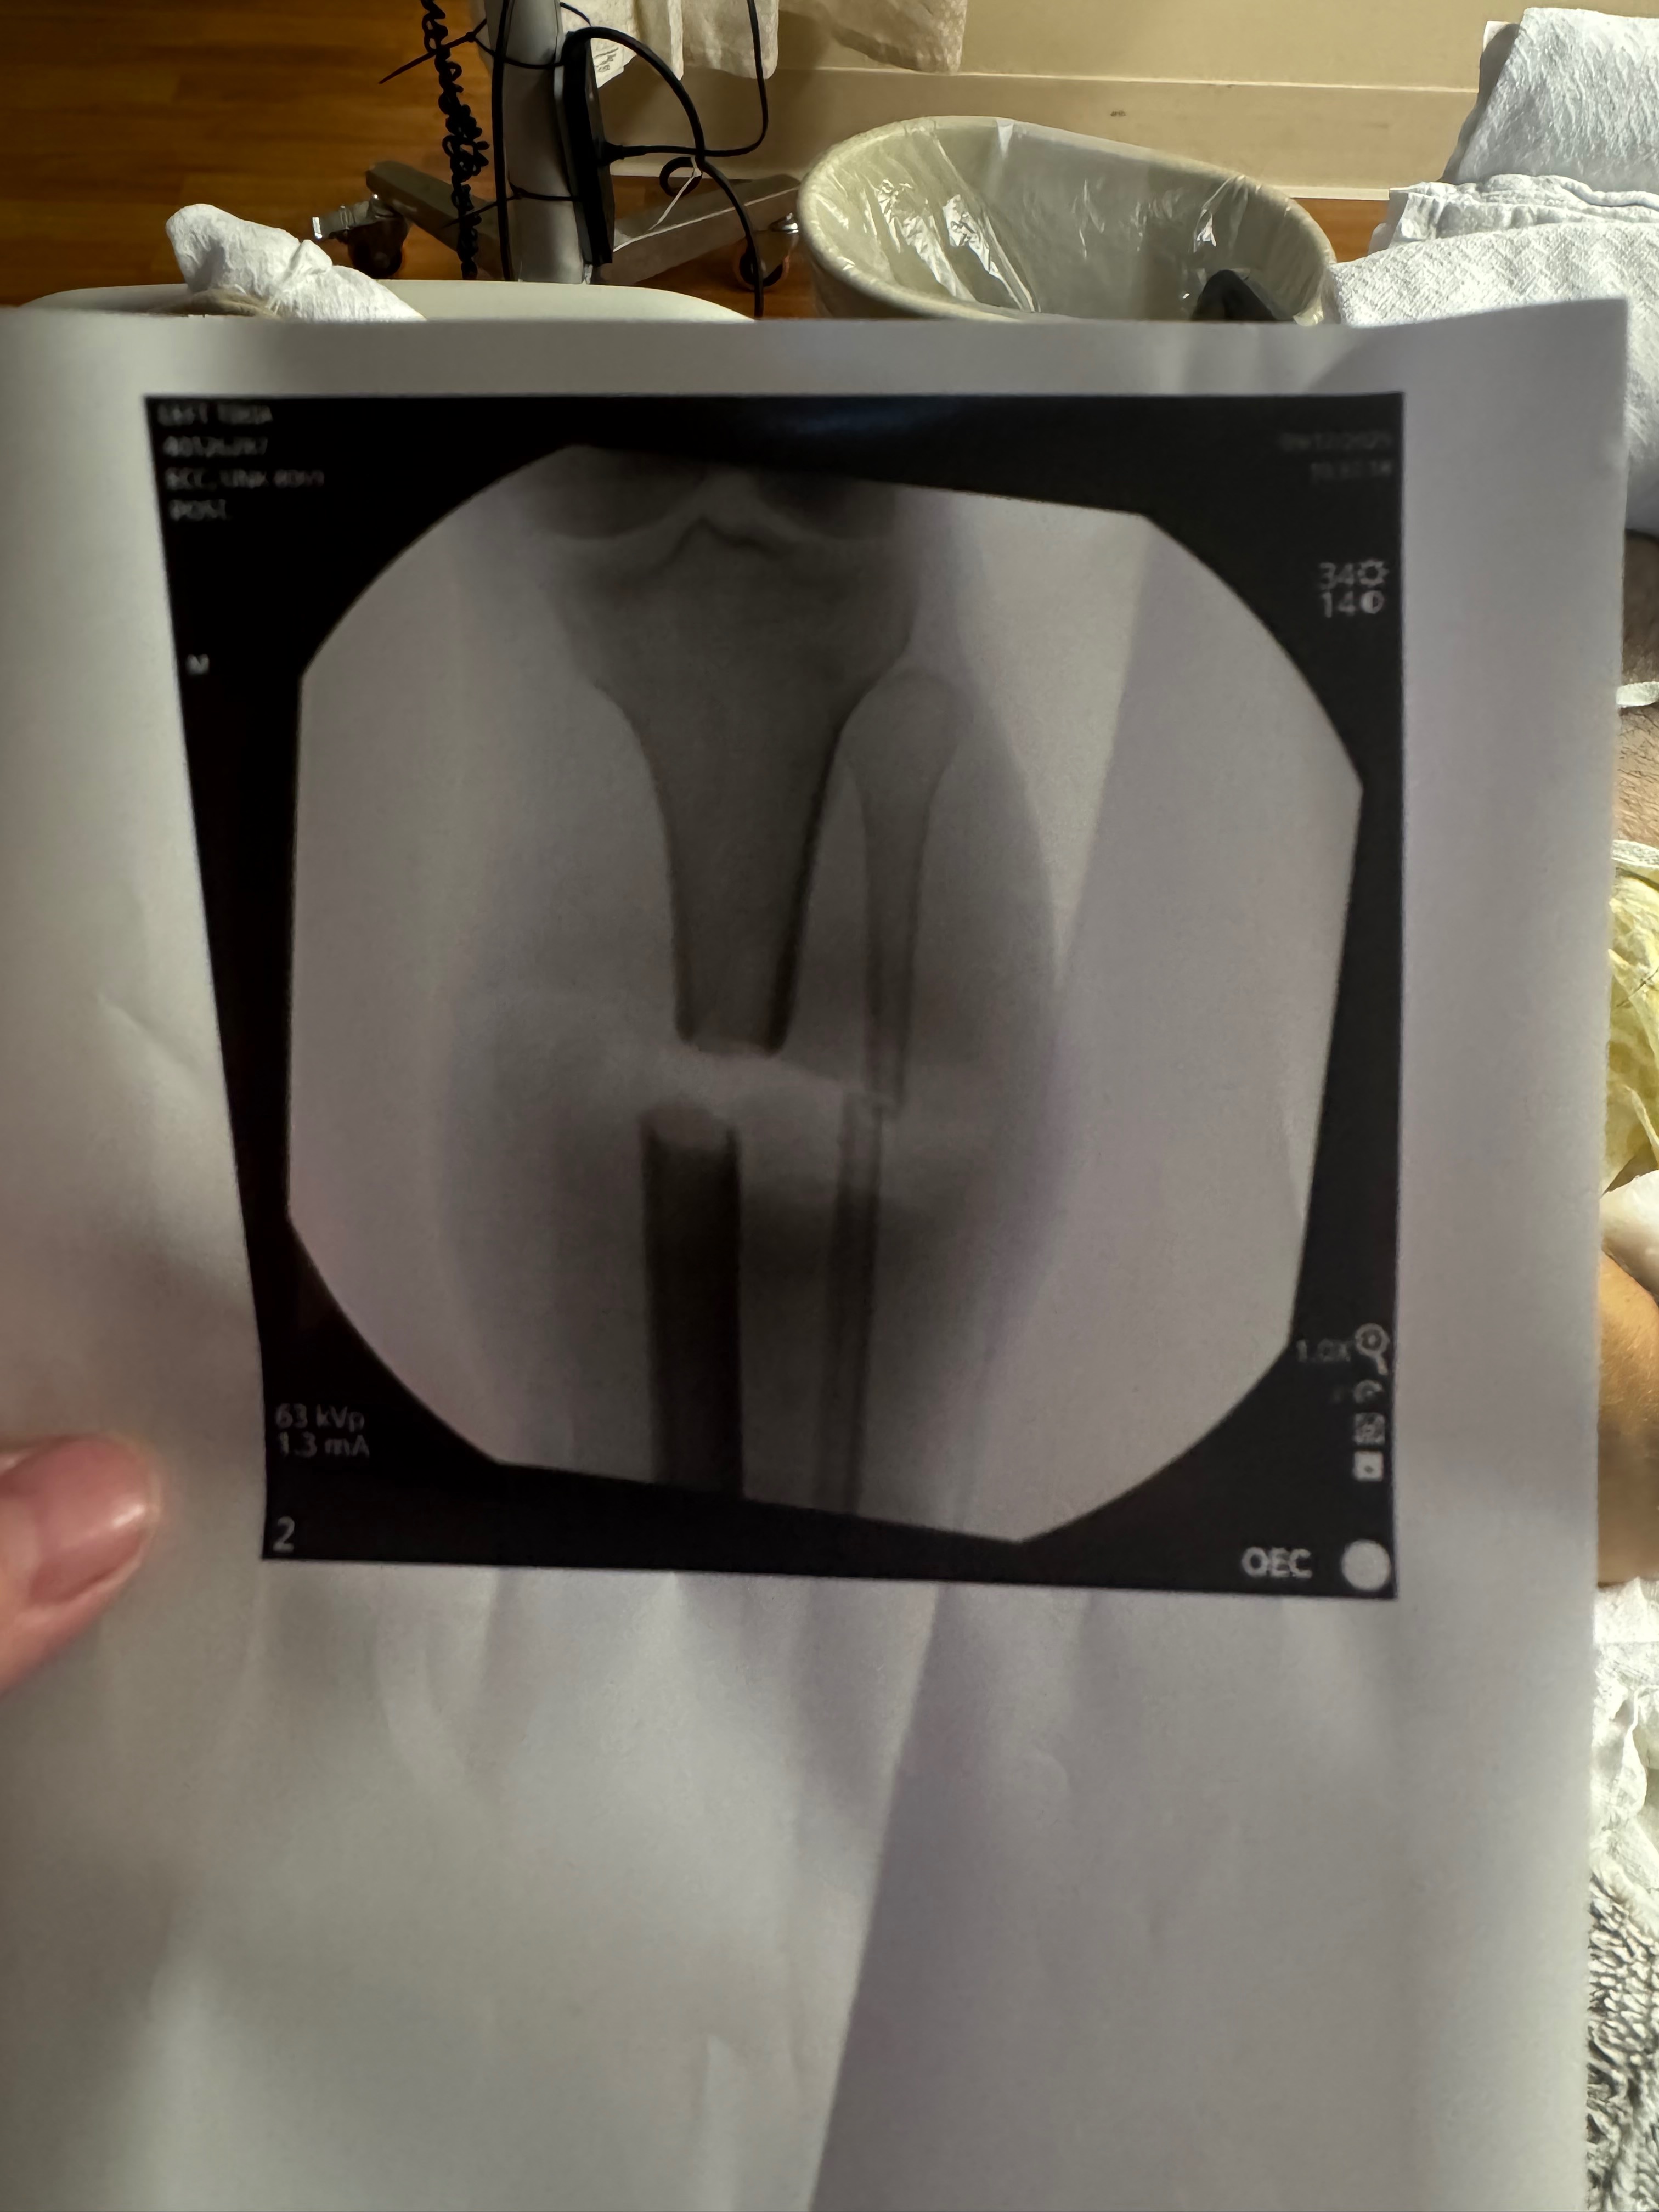

On September 17th, Gage was in a serious accident at work. A freak accident that resulted in both his tibia and fibula bones in his left leg being cut in half with a saw. Gage’s leg was literally hanging on by his calf muscles. He has had one surgery so far and is looking at 1, maybe 2 more surgeries ahead. Not to mention the months of physical therapy and mental rehabilitation from this traumatic injury.